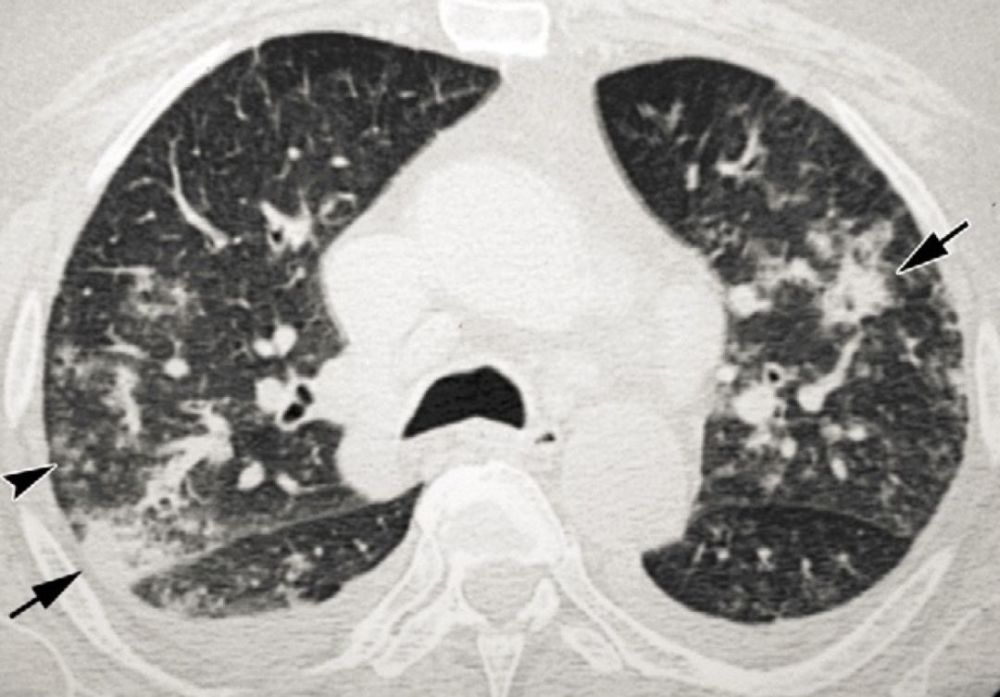

小叶性肺炎CT

小叶性肺炎CT,大叶性肺炎CT

小叶性肺炎ct图片